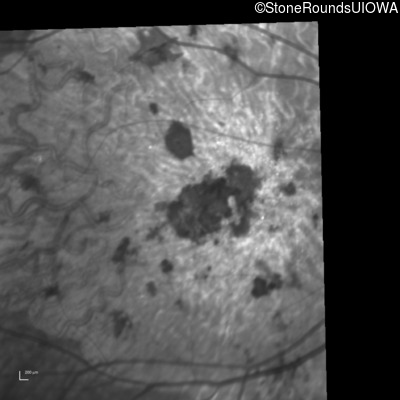

Infrared Fundus Photograph - Right - 20/200 sc

Exemplar